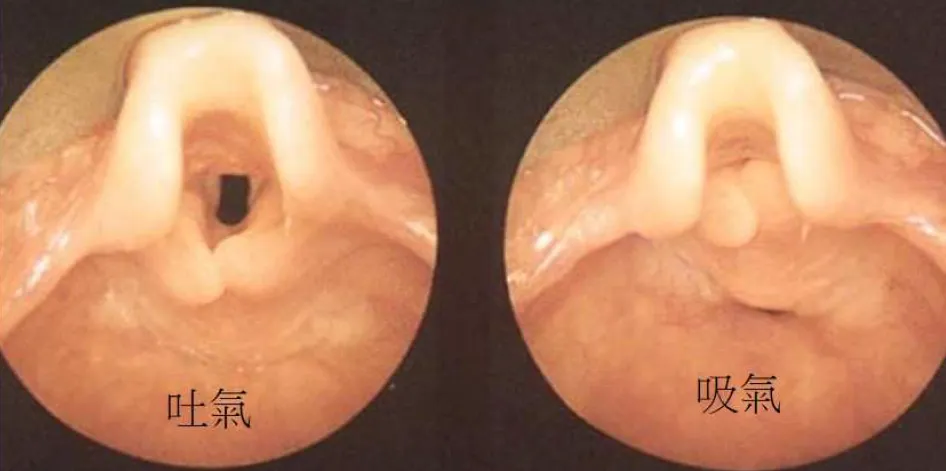

【108-1 醫學(六) 第21題】3個⽉⼤⾜⽉產嬰兒,出⽣3週後家⻑注意到呼吸不順有雜⾳,經⽿⿐喉科醫師評估後安排喉內視鏡檢查,結果如下圖,下列敘述何者正確?